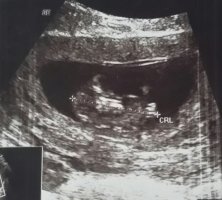

3 TANE DAHA YÜKLEDİM :beybi:

• IMG-20180223-WA0002.jpg

• IMG-20180223-WA0003.jpg

• IMG-20180223-WA0004.jpg